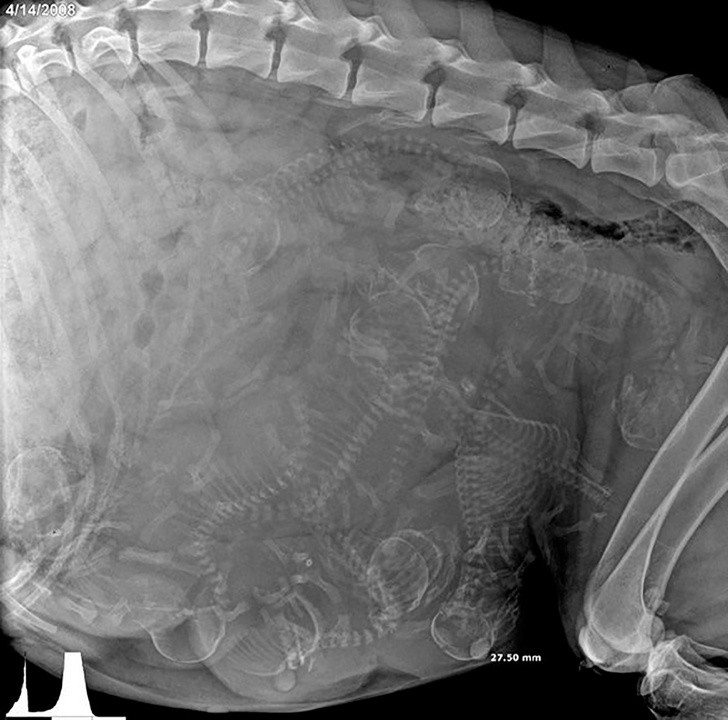

2. Hình chụp X-quang một con chó đang mang thai.